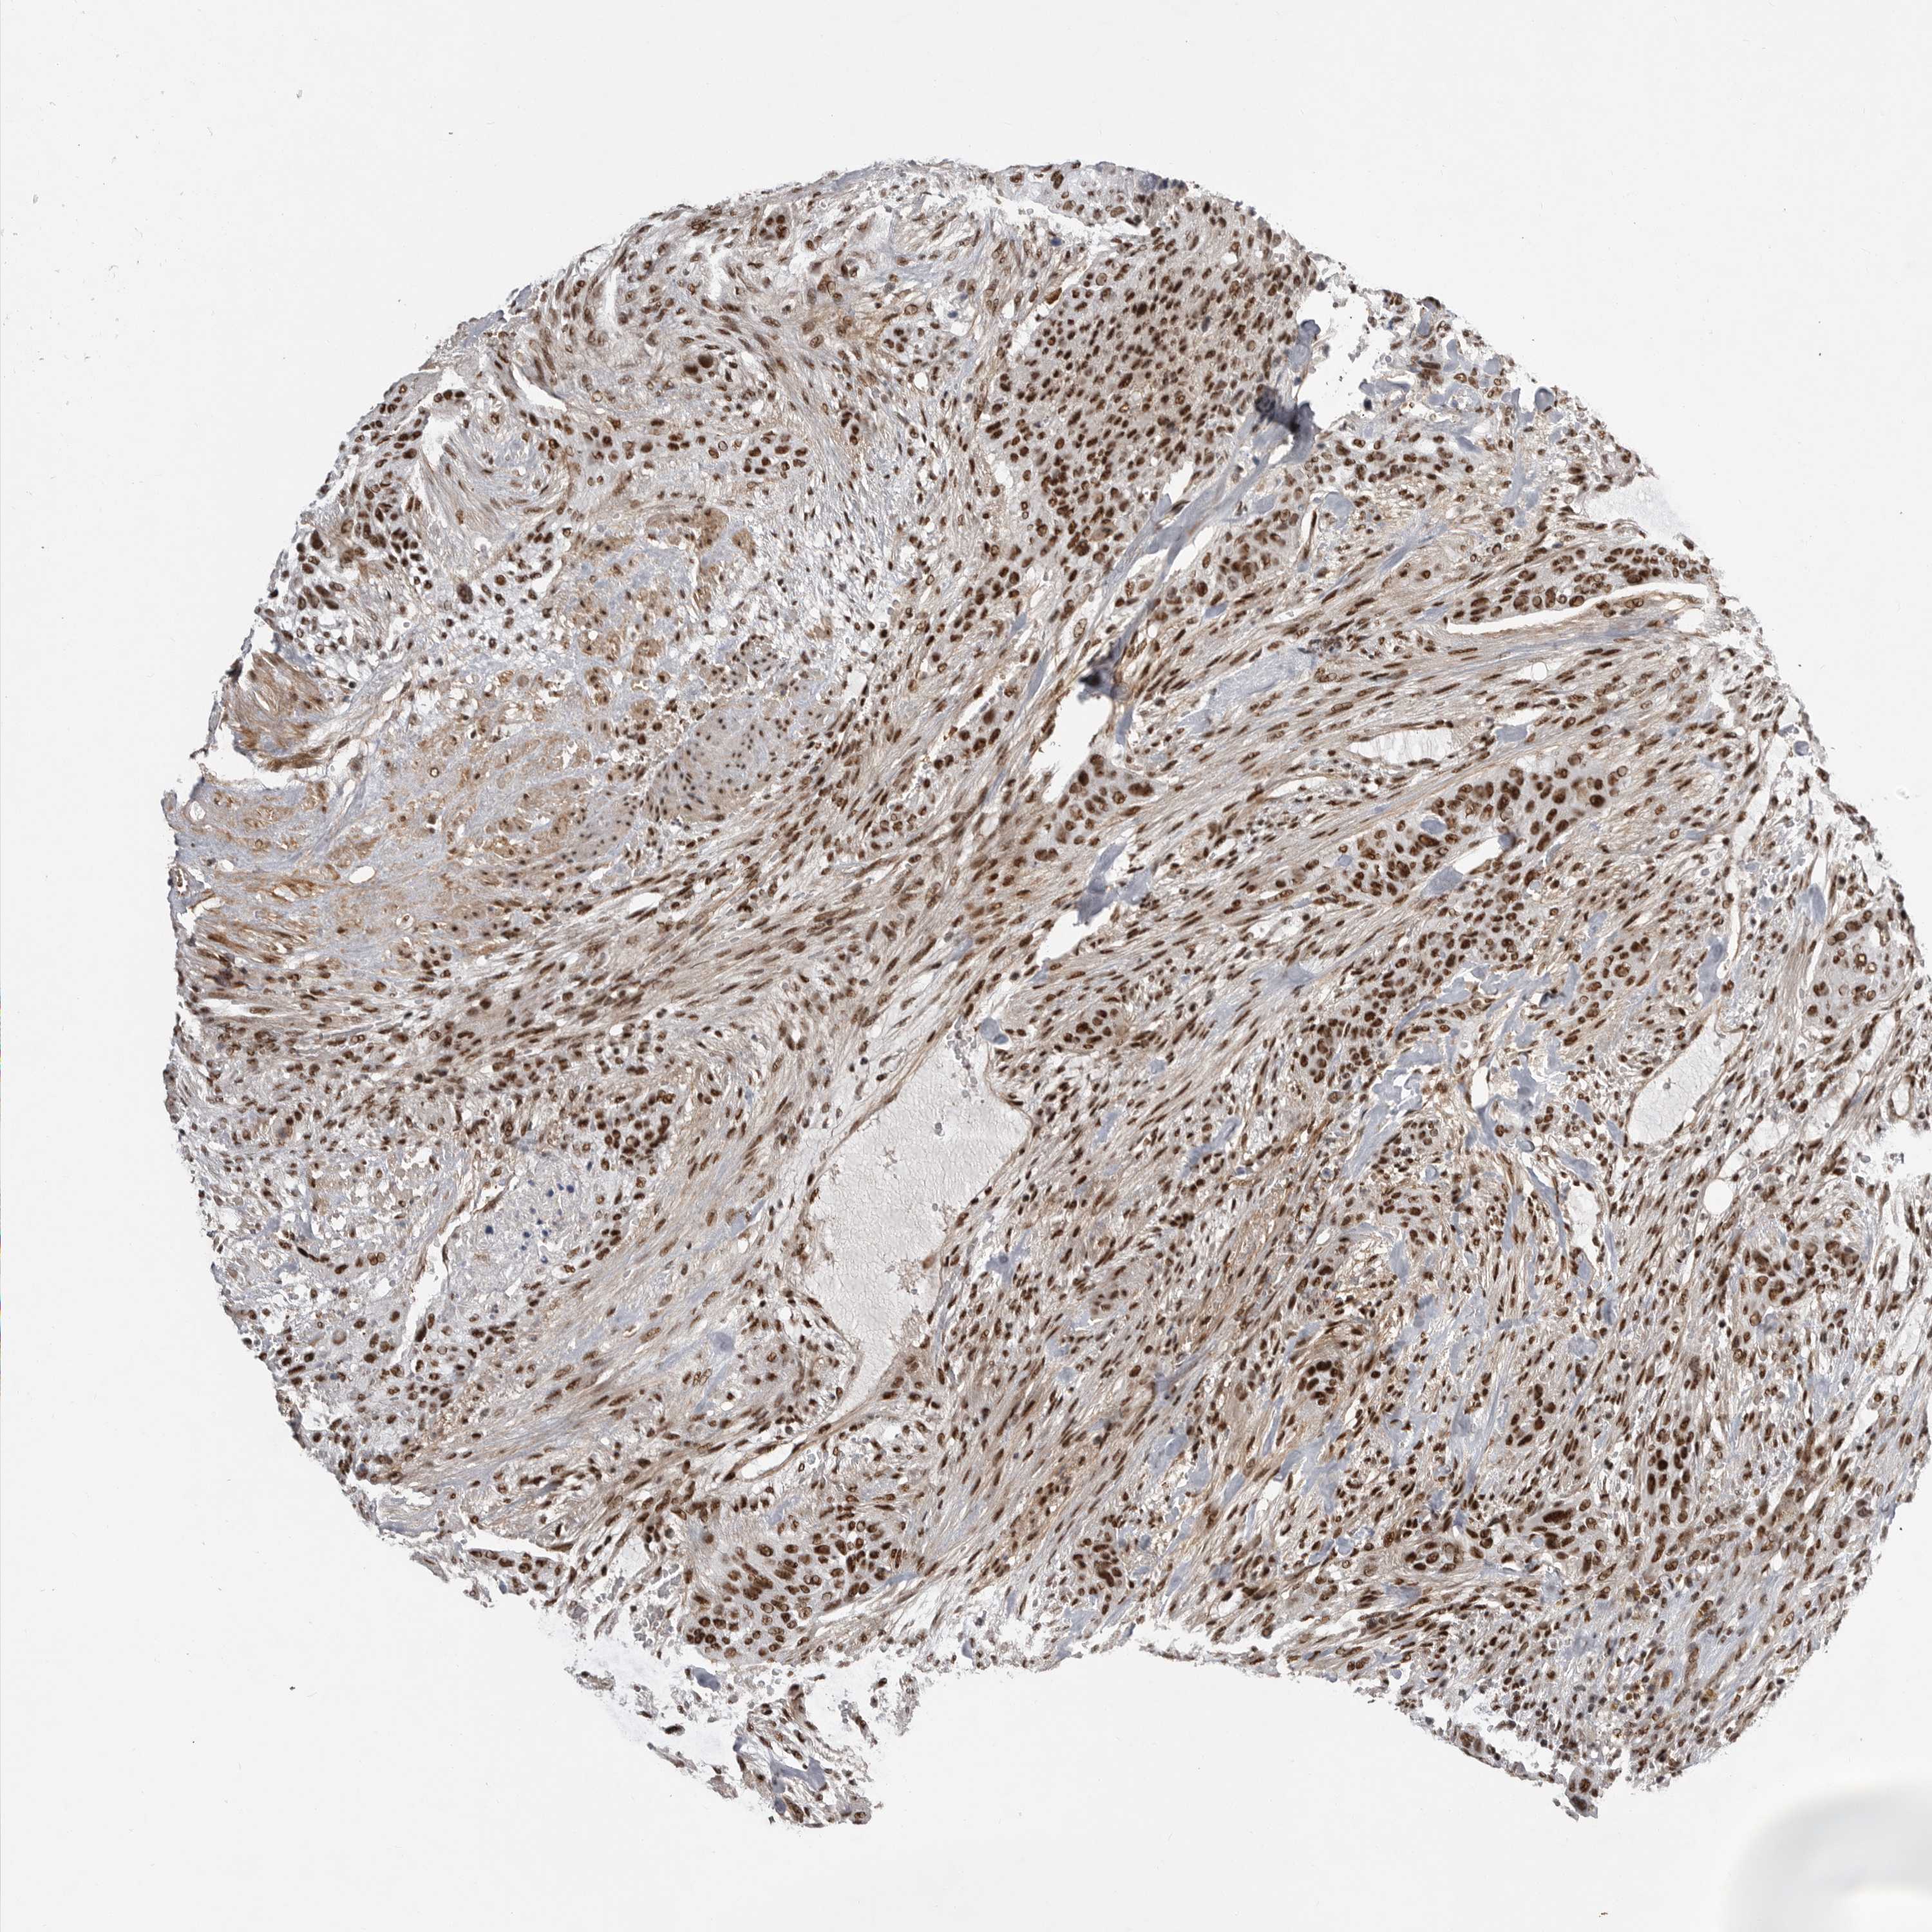

UROTHELIAL CANCER - Protein expressioni

A mouse-over function shows sample information and annotation data. Click on an image to view it in a full screen mode. Samples can be filtered based on level of antibody staining by selecting one or several of the following categories: high, medium, low and not detected. The assay and annotation is described here.

Note that samples used for immunohistochemistry by the Human Protein Atlas do not correspond to samples in the TCGA dataset.

Antibody stainingi

Antibody staining in the annotated cell types in the current human tissue is reported as not detected, low, medium, or high, based on conventional immunohistochemistry profiling in selected tissues. This score is based on the combination of the staining intensity and fraction of stained cells.

Each image is clickable and will lead to virtual microscopy that enables deeper exploration of all samples and also displays staining intensity scores, fraction scores and subcellular localization as well as patient and tissue information for each sample.

Antibody HPA027406

Antibody HPA027417

Antibody HPA027452

Urothelial carcinoma, Low grade

Urothelial carcinoma, High grade